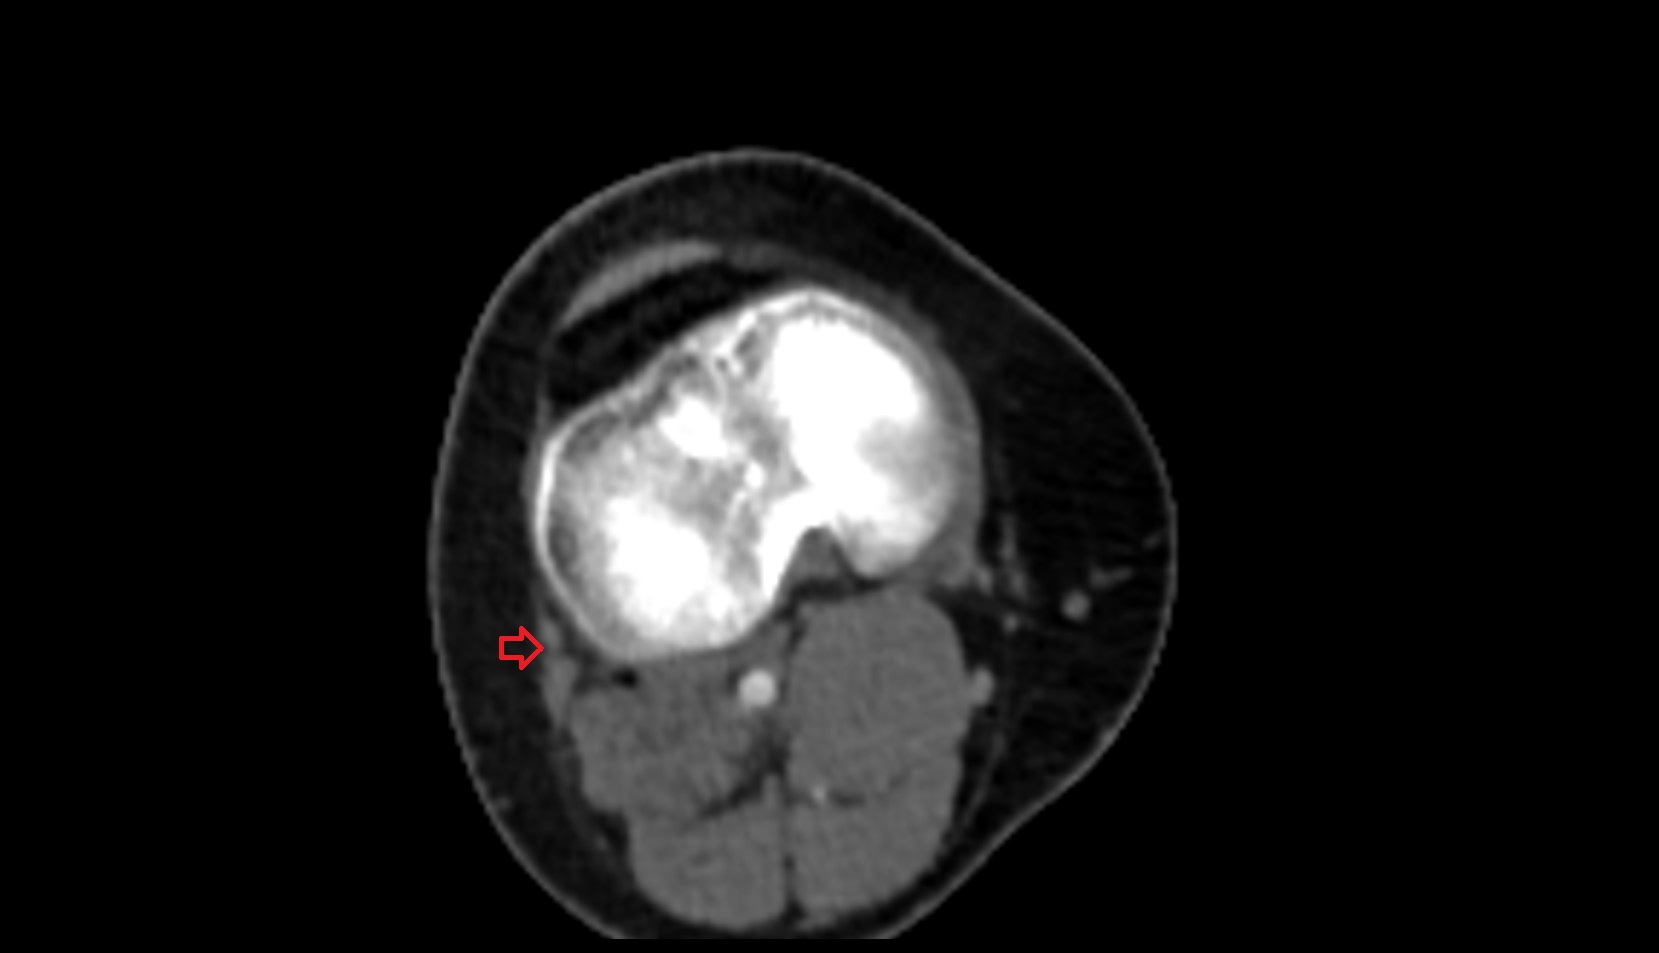

- Knee Joint